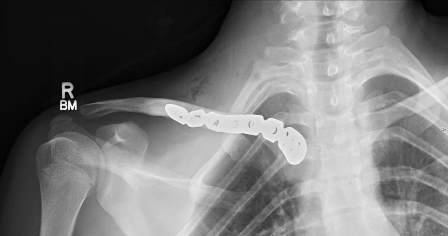

Fig. 4: Intra-operative image showing the rotated medial end of clavicle and disrupted sternoclavicular joint

The patient underwent emergency open reduction through a longitudinal incision along the medial clavicle. Surgical exploration showed the floating fragment, which was rotated and had a partially stripped periosteal sheath (Fig. 4); its medial end had a rough surface, and did not have the appearance of a cartilaginous articular surface, which corresponded to a fracture through the medial physis of the clavicle. Gentle manoeuvres were performed to reduce the fragment. Anatomic reduction and fixation of the lateral fracture with a reconstructive plate (which crossed only the lateral fracture) resulted in reduction of the fracture. Radiographic confirmation of the reduction was obtained and stability was tested with gentle mobilization of the ipsilateral upper extremity and loading of the SC joint. After surgery, the patient was placed in a sling for 4 weeks: progressive resumption of movements and activities was then allowed. After surgery the patient was asymptomatic; examination showed symmetry of the clavicles and of the SC joints, painless and complete range of motion of the left shoulder. Radiographs showed complete consolidation at three months (Fig. 5). The patient has resumed full activities and sports without problems subsequently.

Fig. 5: Three months post-operative X-ray